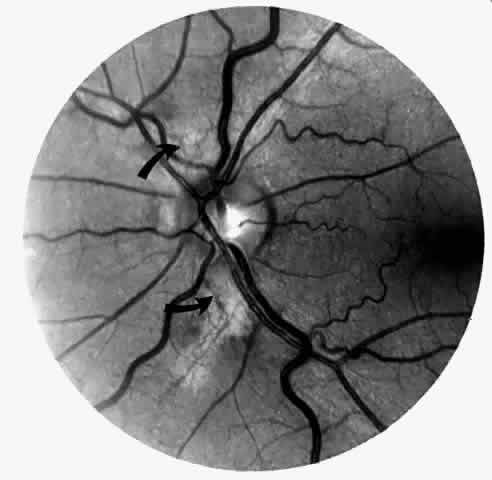

Vascular Tortuosity

Dilation and tortuosity of the retinal veins was one of the first recognized abnormalities of sickle cell eye disease. Although it is not pathognomonic of sickle cell disease, it reportedly occurs in up to 47% of patients with homozygous sickle cell anemia and 32% of patients with SC disease (Fig. 4).70 The significance of this venous tortuosity is unknown, and the incidence does not appear to be related to age.71

Fig. 4. A. Generalized vascular tortuosity, predominantly venous, in a patient with homozygous sickle cell anemia. B. Localized macular venous tortuosity in a patient with SC disease.